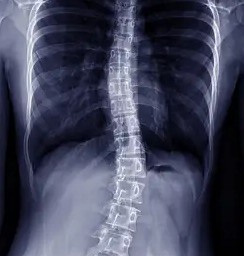

Scoliosis is a deformation that affects the spine. Most common in adolescents, scoliosis causes the spine to curve from side to side, creating a C or S shape. In severe cases, the curves can be greater than 45 degrees. Curves like this are extreme, but fortunately, they are easily correctable with scoliosis surgery.

The procedure involves the insertion of hooks and screws into the spinal structure. These are then connected to a rod, which stabilizes the spine while the vertebrae are fused with a bone graft. By stabilizing and fusing the bones, the surgeon can stop the condition’s progression, reduce the deformity, and help the patient become more balanced.